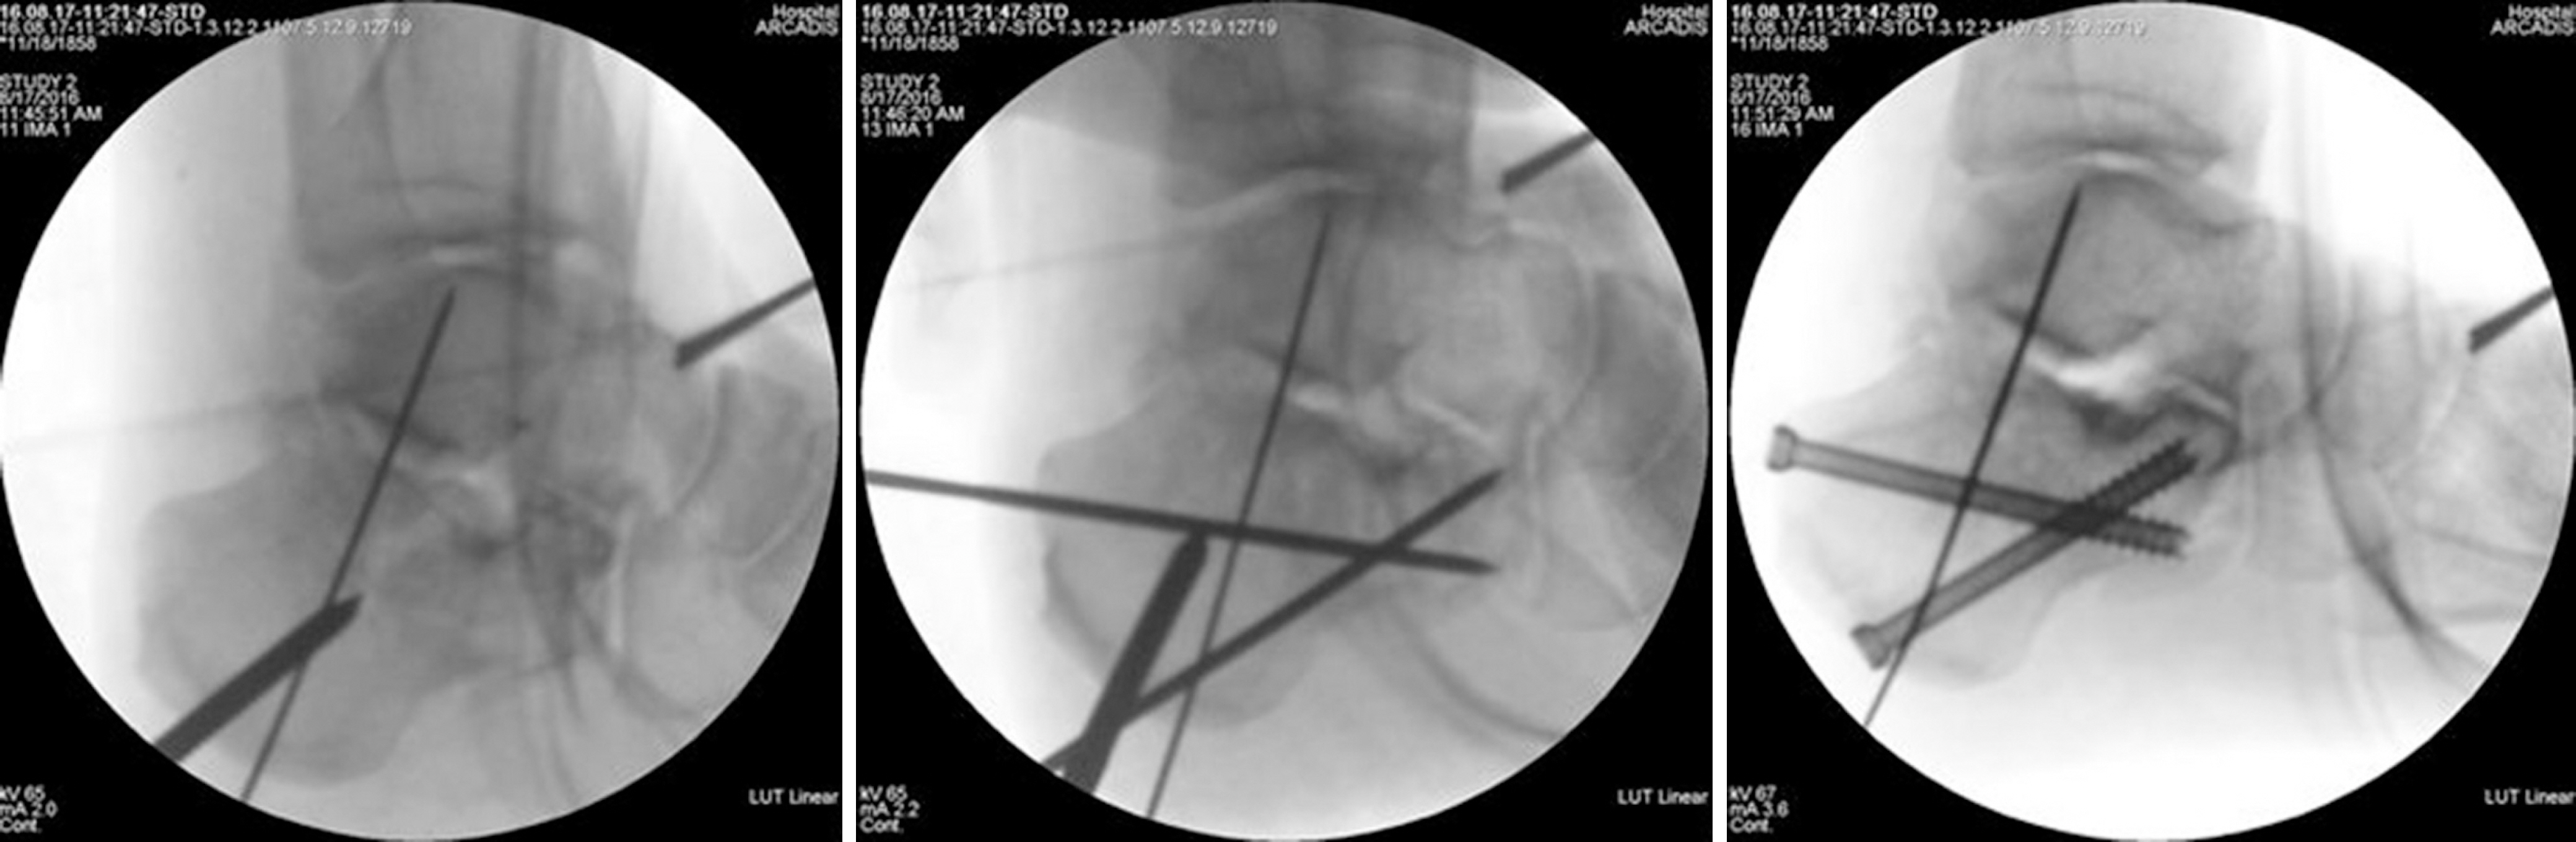

Fig. 1.

(A) Preoperative X-ray and computed tomography showing a Sanders type IV and joint depressive type calcaneal fracture. (B) The postoperative X-ray showing restoration of the of Böhler's angle, Gissane's angle, and the calcaneus height, length, and width.